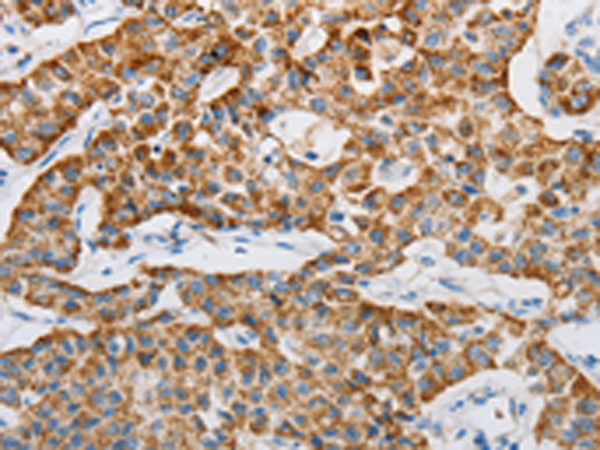

分类: 科研抗体货号: P11013别名: ASK1, MEKK5, MAPKKK5应用: IHC反应种属: Human, Mouse